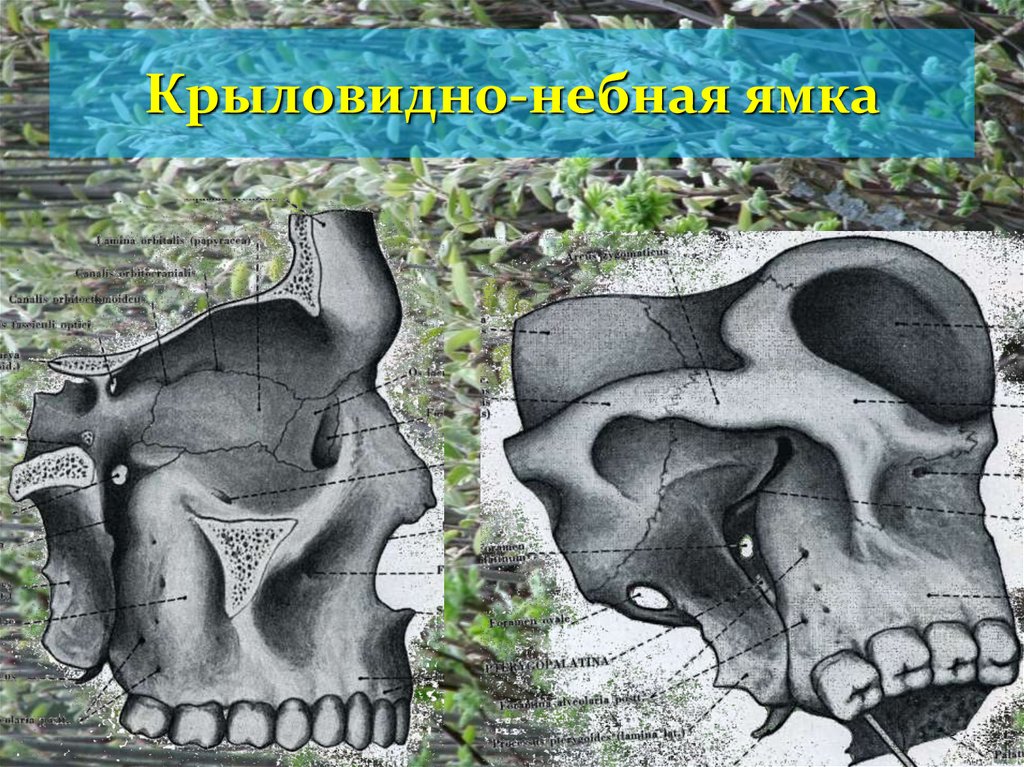

Анатомические особенности: фотографии ямок черепа, височной и подвисочной крылонебной